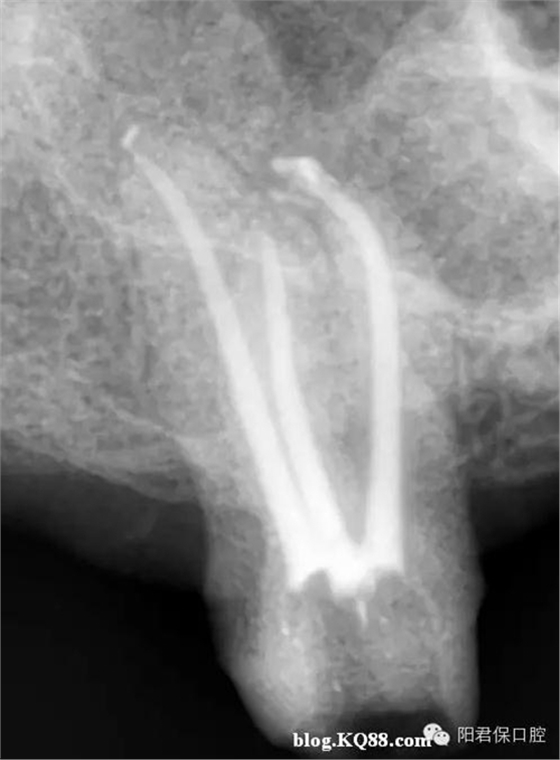

患者:姜XX 性別;女 年齡:65 根據(jù)齲壞程度、患者的癥狀、修復(fù)需要,且對收費及牙髓處理均征得同意后第一次行右下4、5,左下4、5、6;第二次行左下2,右下2 ,右上7一次性根管治療術(shù)。

術(shù)后見右下4,左下4均有側(cè)支充填,且位置對稱,左下6近中根中部有側(cè)支;左下5、左下6遠中根管均多個開口。

熱牙膠垂直加壓后有封閉劑和牙膠超填,但無術(shù)后反應(yīng)。